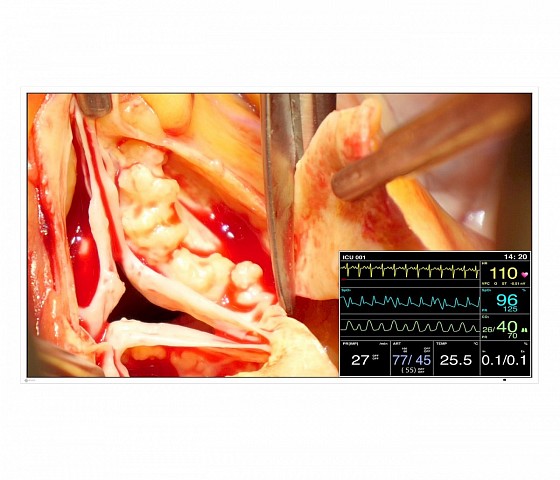

This 49” widescreen monitor is ideally suited for viewing medical images under OR conditions. Numerous input and output signals, image combination capabilities, and gamma models pre-calibrated at the factory enable its use within the widest range of applications. With its fan-free design and water-tight, easy to clean front, the monitor is perfectly suited for sterile hospital environments.

- Numerous video inputs and outputs for increased connectivity

- Flexible image arrangement thanks to the Picture-in-Picture (PiP) and Picture-at-Picture (PaP) functions